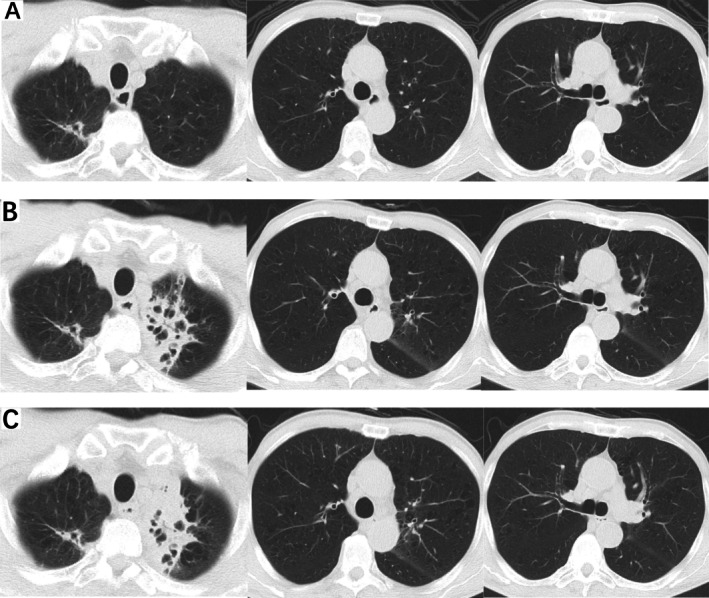

一名64岁男性,有肝细胞癌病史,长期口服lenvatinib治疗,因“咳嗽”两次住院。在住院期间,患者接受了多次支气管镜检查,并送洗液进行病原体检测,结果为阴性。最后,通过下一代测序(NGS)检测到堪萨斯分枝杆菌。考虑到患者肝脏储备不良,我们决定不启动靶向抗菌治疗并停用lenvatinib。停用lenvatinib两个月后,患者咳嗽和胸闷症状有所改善。2025年3月18日随访胸部计算机断层扫描(CT)显示病变消退。

A 64-year-old man, with a history of hepatocellular carcinoma and long-term oral lenvatinib treatment, was hospitalised in our institution twice due to 'cough'. During hospitalisation, the patient underwent multiple bronchoscopies, with lavage fluid sent for pathogen testing, which returned negative results. Finally, Mycobacterium kansasii was detected via next-generation sequencing (NGS). Considering the patient's poor hepatic reserve, we decided against initiating targeted antimicrobial therapy and discontinued lenvatinib. Two months after stopping lenvatinib, the patient's symptoms of cough and chest tightness improved. A follow-up chest computed tomography (CT) on March 18, 2025, showed resolution of the lesions.